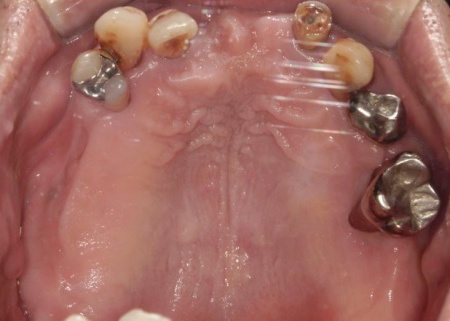

拝見したところ、患者様は上前歯が数本欠損しており、残っている歯を利用して橋渡しのように歯を補うブリッジ治療が行われていました。しかし、転倒による衝撃でブリッジが外れていました。

また、患者様は重度の歯周病によって歯を支える骨が減少し全体的に歯が揺れていました。

残っている上の歯7本(左右上側切歯、左右上犬歯、左右上第1小臼歯、左上第1大臼歯)と右下奥歯2本(第2大臼歯、第3大臼歯)は残すことが難しく抜歯が必要な状態です。

以上のことから、抜歯を行ったうえで歯を補う治療が必要と診断しました。